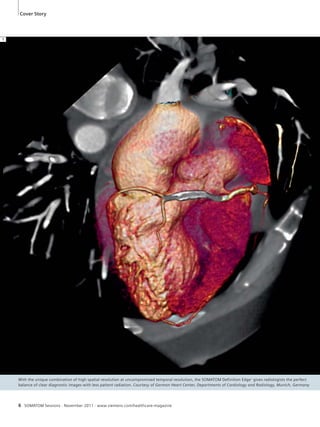

Cover Story

With the unique combination of high spatial resolution at uncompromised temporal resolution, the SOMATOM Definition Edge1 gives radiologists the perfect

balance of clear diagnostic images with less patient radiation. Courtesy of German Heart Center, Departments of Cardiology and Radiology, Munich, Germany